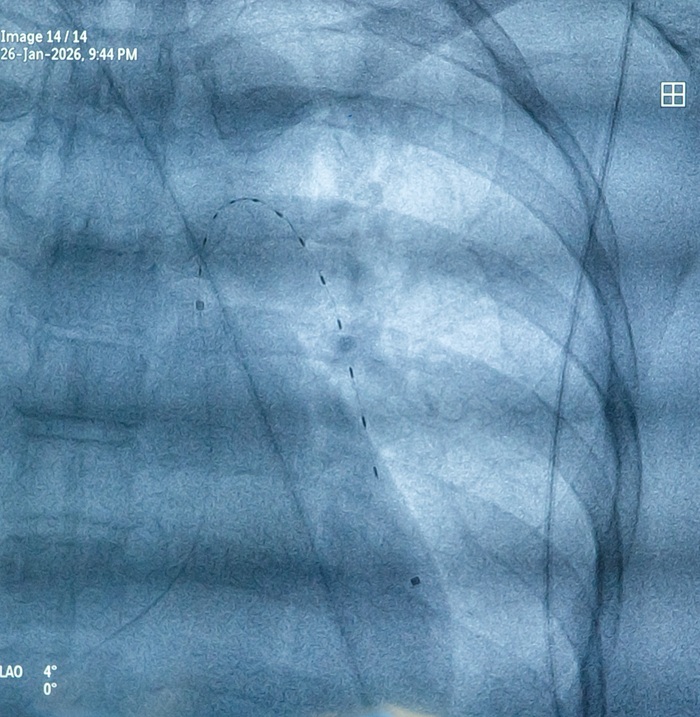

EKOS is a medical technology designed to safely and rapidly dissolve blood clots in pulmonary embolism. The procedure is minimally invasive (without major surgery), using a catheter (a small tube inserted into a blood vessel) to deliver clot-dissolving medication directly to the site of blockage.

EKOS also utilizes targeted ultrasound waves directed at the clot. These waves help loosen and separate fibrin (the main protein that forms blood clots), allowing the medication to penetrate deeper and work more effectively in dissolving the clot.

- A catheter (small tube) is inserted into a blood vessel and guided directly to the clot in the lungs

- Thrombolytic medication is delivered directly through the catheter to the blockage

- EKOS generates ultrasound waves targeted at the clot

- The ultrasound waves help loosen and thin the fibrin structure, making the clot more open

- This process exposes more drug receptor sites, allowing the medication to work more effectively

- Acoustic streaming (energy flow from ultrasound waves) helps push the medication deeper into the clot

- This combination enables faster, more even clot dissolution with lower medication doses